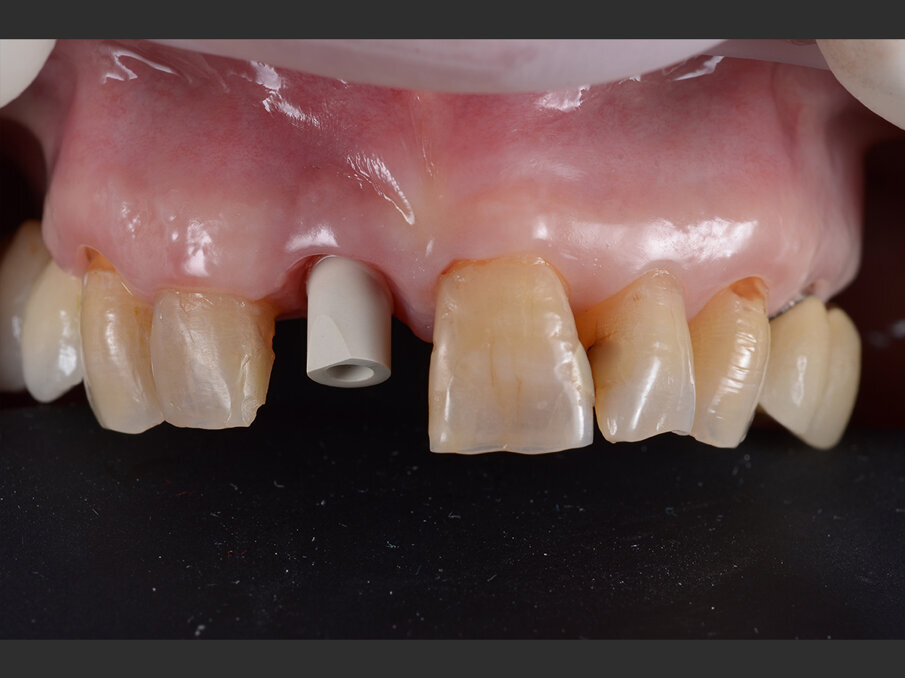

La paziente, donna di 60 anni, non fumatrice ed in buone condizioni di salute generale, si presenta in studio con sintomi di pulpite irreversibile a carico dell’elemento 1.1. L’esame clinico (Figg. 1a, 1b) e radiografico (Fig. 2a) confermano la presenza di una lesione cariosa radicolare che ha colpito il versante mesiale.

Fig. 1a - Valutazione pre-operatoria - visione frontale: l’elemento 1.1 è sintomatico e mostra segni e sintomi di pulpite irreversibile.

Fig. 1b - Valutazione pre-operatoria - visione palatina: è possibile apprezzare la lesione cariosa corono-radicolare.